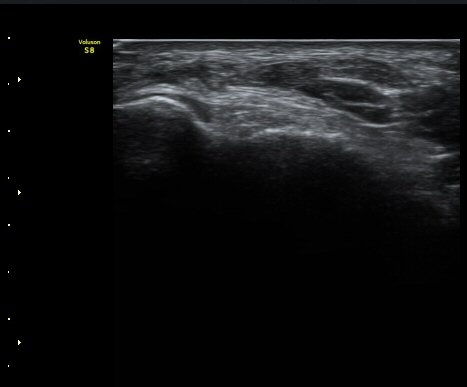

Àüºñ°ñ°æ°ñÀδë Á¾´Ü¸é°Ë»ç¿¡¼­ ƯÀÌ ¼Ò°ßÀ» º¸ÀÌÁö ¾Ê´Â´Ù(±×¸² 2).

±×¸²2) Àüºñ°ñ°æ°ñÀδë Á¾´Ü¸é°Ë»ç±Û